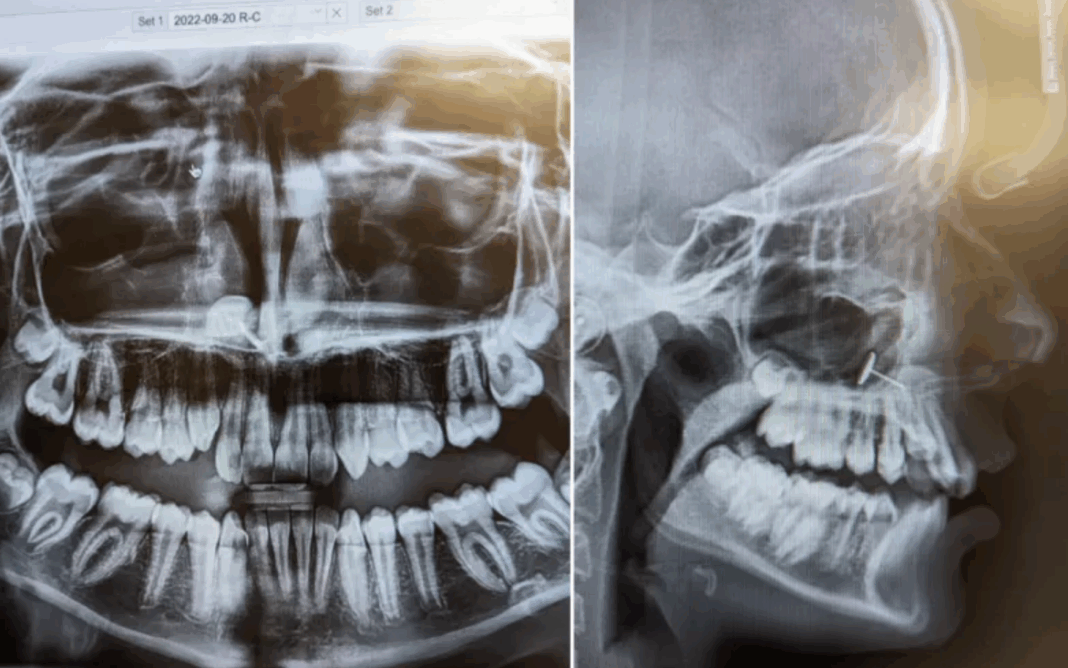

Μια μητέρα στην Ουάσινγκτον πήγε την 13χρονη κόρη της στον οδοντίατρο για μια ρουτίνα ακτινογραφία, αλλά ανακάλυψε κάτι απροσδόκητο: ένα κομμάτι μετάλλου σφηνωμένο στα ιγμόρεια της κόρης της.

«Ο ορθοδοντικός επέστρεψε στο δωμάτιο και έβαλε τις ακτινογραφίες στην οθόνη», είπε η Οφέλια στο Newsweek. «Τις είδαμε όλοι ταυτόχρονα και πέρασαν αρκετά λεπτά προσπαθώντας να καταλάβουμε τι βλέπαμε».

Αυτό που έβλεπαν φαινόταν να είναι ένα μικρό κομμάτι μετάλλου που είχε σφηνωθεί στα ιγμόρεια της μύτης της κόρης της. Η Οφέλια δεν είχε ιδέα πώς βρέθηκε εκεί, αλλά η κόρη της ήξερε ακριβώς τι είχε συμβεί.

Όλα αυτά μέχρι την επίμαχη επίσκεψη στον ορθοδοντικό και την ακτινογραφία που αποκάλυψε τα πάντα. Η Οφέλια δημοσίευσε τις εικόνες των ακτινογραφιών στον λογαριασμό της στο Reddit, που έγιναν αμέσως viral.